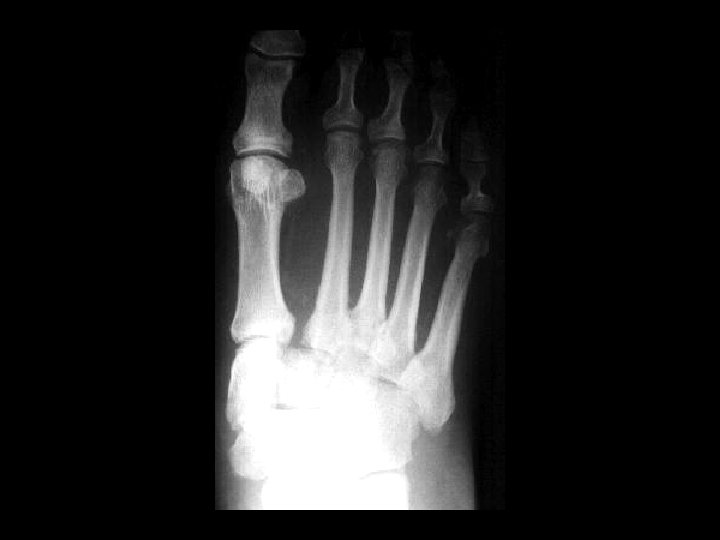

Homolateral Lisfranc farcture/dislocation • Findings – Widening between the base of 1 st and 2 nd metatarsals. – lateral subluxation of the second through fifth metatarsals • dislocation is relative to the cuneiforms: – homolateral – divergent (1 st MT goes medial) • can be due to trauma or in patients with diabetic neuropathy